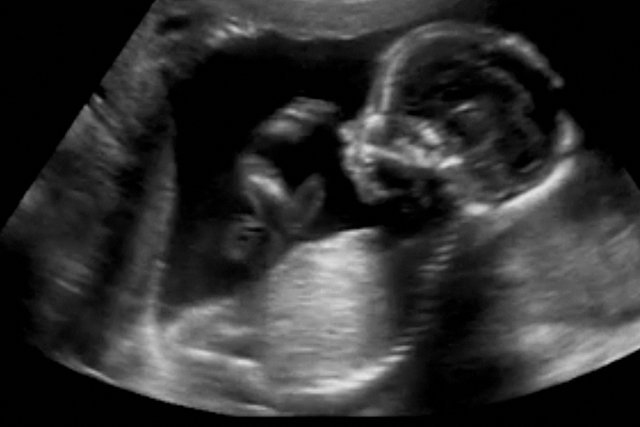

Genetycznym ojcem dziecka jest zaś nienarodzony brat bliźniak 34-latka. Brat zmarł na początku trwania ciąży, ale cześć jego komórek trafiła do krwi drugiego dziecka, czyli późniejszego dawcy nasienia, który posiada teraz komórki różniące się genetycznie i jest przez to tzw. ludzką chimerą. Materiał genetyczny jego śliny, pobieranej przy wykonywaniu testów na ojcostwo, różni się od materiału genetycznego zawartego w jego nasieniu.